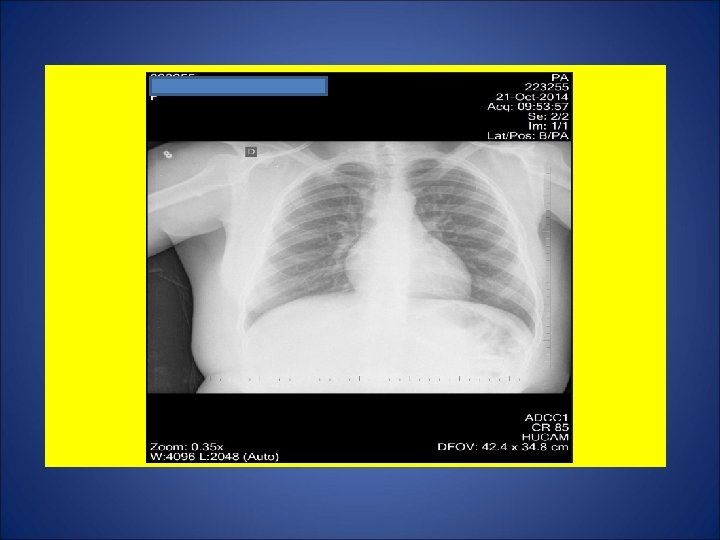

CASO 4, masculino, 30 anos, natural de Vitoria (ES), residente na Serra (ES), pedreiro. Há 2 meses e meio, tosse não produtiva, sudorese noturna, calafrios, adinamia. Surgimento de febre 20 dias e de expectoração purulenta 15 dias após. Episódios de escarros hemoptóicos 10 dias atrás e em 18 Out. Há 1 mês, dor em hemitórax esquerdo agravada com a tosse. Há 20 dias, dispnéia aos médios esforços. Durante os últimos 15 dias, perda de 10 Kg. Negou contato com casos de tuberculose. Negou tuberculose prévia. Negou tabagismo e etilismo. HIV negativo. Ex. fisico: P=73 Kg, Altura= 1, 63 m, IMC= 27, 5 Kg/m 2 (discreto sobrepeso), FC = 110 bpm. Marca de BCG em MSD.

ESCARROS ESPONT NEOS: 1º) 20/10/14: 10 m. L – PURULENTO - 30 min: BAC NEG - TRM: M. tuberculosis NÃO DETECTADO – CULT em curso 2º) 20/10/14: 10 m. L – MUCOPURULENTO – 30 min: BAC NEG – CULT em curso 3º) 21/10/14: 10 m. L – MUCÓIDE – 30 min: BAC NEG – CULT em curso